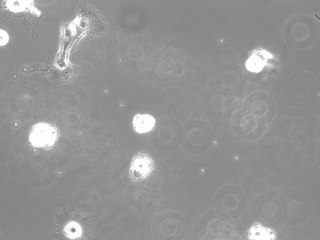

Serap Akıncıoğlu: Apoptosis - hücre intiharı